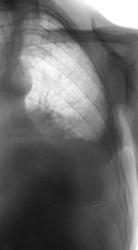

Правосторонний экссудативный плеврит с "затеканием" экссудата в главную междолевую щель. Плевра в междолевых щелях утолщена.